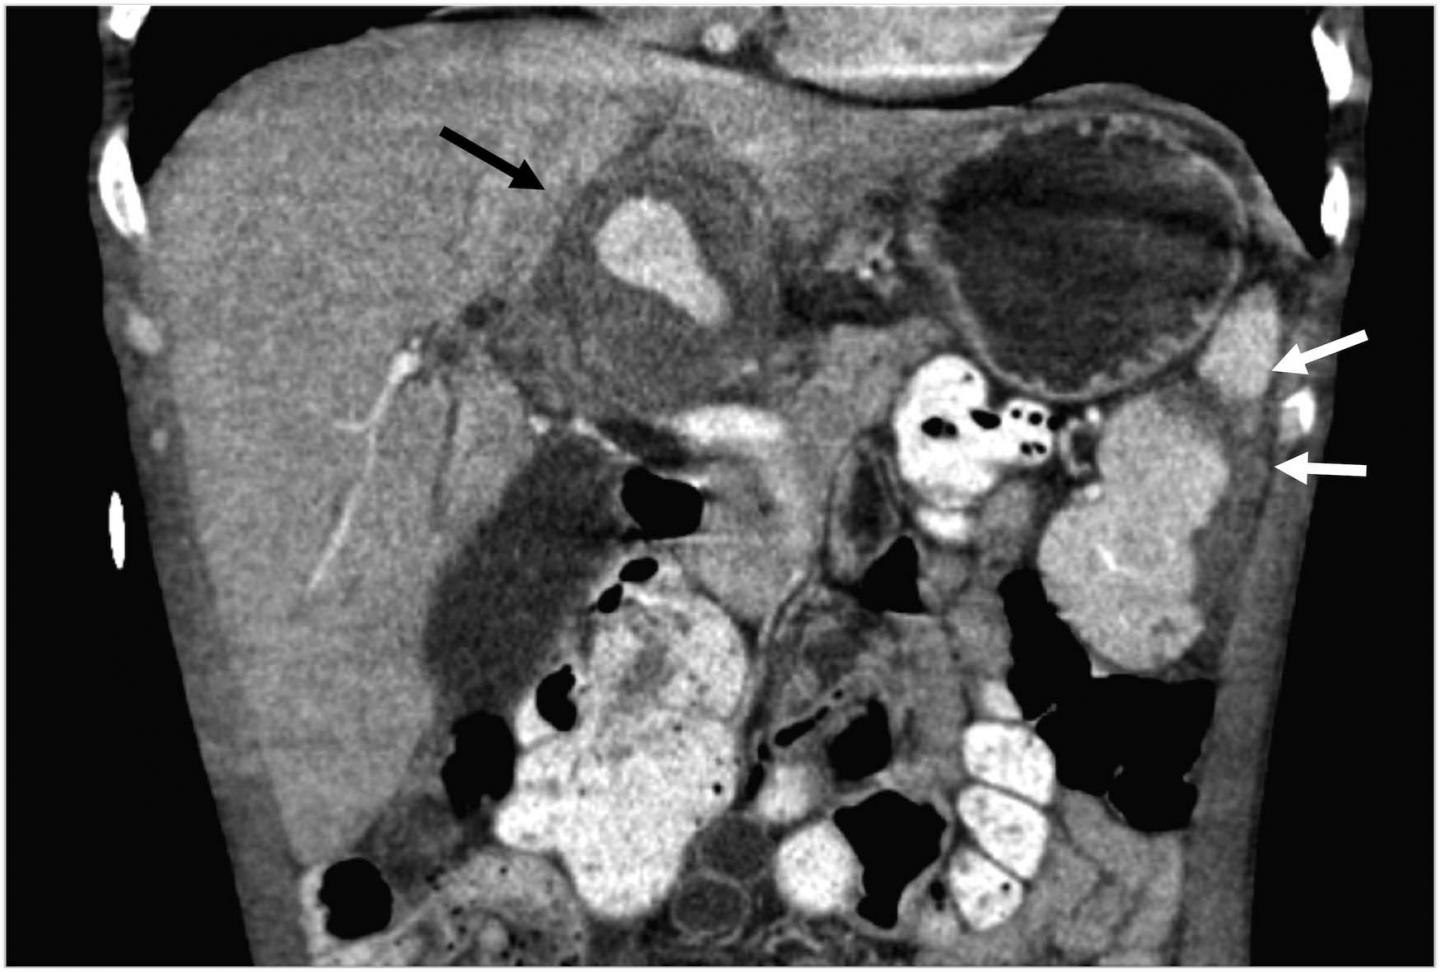

"Complications were most frequently related to skin and soft tissue infections caused by the use of non-sterile needles," Dr Flores said. "In some cases, we found septic emboli in the lung or brain. As these patients start having to access larger veins, they become more prone to these types of infections."

There were 1,673 imaging exams performed, including 779 X-rays, 544 CTs, 292 MRIs and 58 ultrasounds. Imaging results often provided critical information, such as when physicians changed the management plan for a patient with a substance-abuse-related lumbar spine infection after CT scans showed the involved nerves.